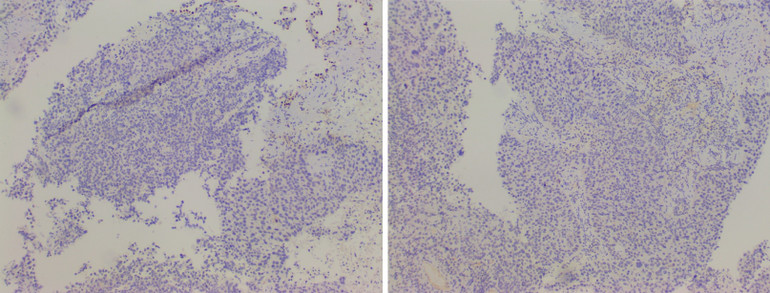

| Kết quả xét nghiệm hóa mô miễn dịch của bệnh nhân. |

Phát hiện các dấu hiệu bất thường, bác sĩ chỉ định xét nghiệm mô bệnh học, chẩn đoán ung thư biểu mô không tế bào nhỏ. Tiếp tục thực hiện xét nghiệm hóa mô miễn dịch để chẩn đoán xác định, kết luận tình trạng của bệnh nhân là ung thư biểu mô thần kinh nội tiết tế bào lớn kết hợp ung thư biểu mô vảy kém biệt hóa (giai đoạn T2bNxMx).

Giải phẫu bệnh được coi là tiêu chuẩn vàng trong chẩn đoán bệnh lý ác tính này với 5 tiêu chuẩn như sau: Tế bào mang đặc điểm ung thư biểu mô không tế bào nhỏ với cấu trúc hình thái thần kinh nội tiết (bè, dải, hàng rào, giả hoa hồng); tỷ lệ nhân chia cao (>10 NC/10HPF); hoại tử mức độ nhiều; có thành phần u mang đặc điểm tế bào học của nhóm ung thư biểu mô không tế bào nhỏ khác; IHC: Tế bào u dương tính với dấu ấn thần kinh nội tiết và dấu ấn hóa mô của thành phần ung thư biểu mô không tế bào nhỏ tương ứng.